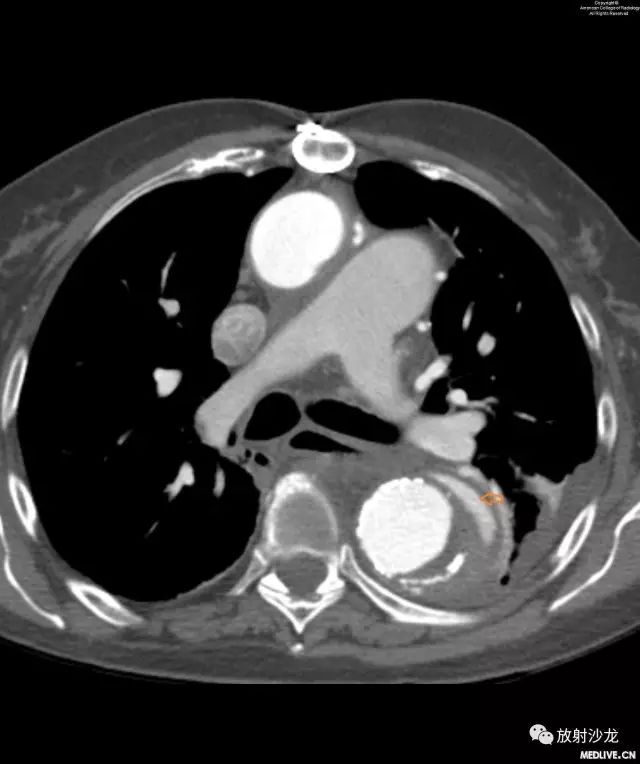

图1和图2:图像显示主动脉结移位。图1是患者一两个月前在另外一次主诉不同的随访中进行的检查结果。与图1相比,图2的移位显而易见。

图3和图4:CT平扫和增强扫描显示由于壁内血肿(intramural hematoma,IMH)而移位的主动脉钙化。注意IMH呈稍高密度影,这提示出血是急性的。